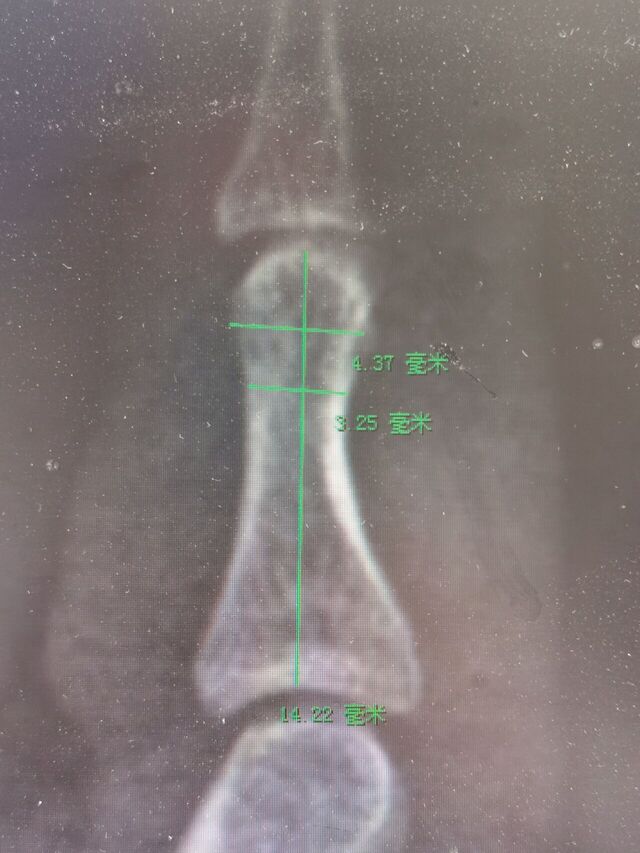

中节指骨宽度10mm厚度4mm

没有合适的截骨摆锯

只能用克氏针并排打孔,然后用骨刀截骨